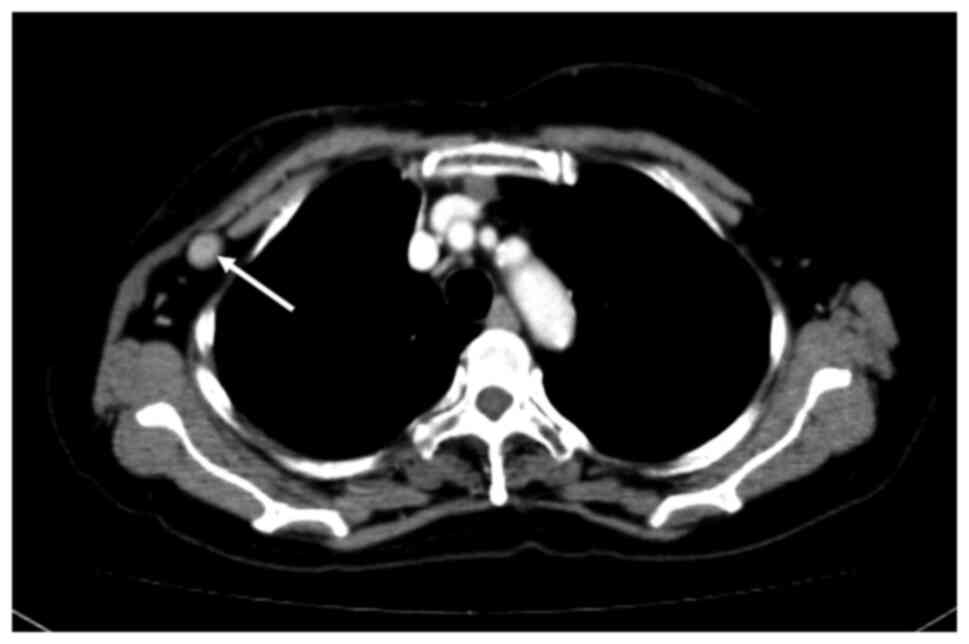

A 67-year-old woman who was diagnosed with T1cN0M0 breast cancer (Luminal A type) underwent total mastectomy and SNB. Since the SN showed no metastasis, axillary lymph node dissection was omitted. Immediate breast reconstruction with an LD flap was simultaneously performed. Three years after the surgery, regular postoperative ultrasonography (US) follow-up during hormonal therapy showed axillary lymph node enlargement. US-guided fine-needle aspiration cytology (FNAC) of the axilla was positive for malignancy. CT showed swelling of a lymph node behind the LD flap (Fig. 2). Since there was no metastasis to other organs, axillary lymph node dissection was performed. The intraoperative findings are shown in Fig. 3. The skin was incised along the anterior axillary line, as in the first surgery. When the LD muscle was retracted caudally, the enlarged lymph node could be identified. The axillary vein was carefully preserved when cutting along the side of the pectoralis major and minor muscles. The thoracodorsal bundle was also identified and preserved. The surgical field was, however, very limited, because the LD muscle passed through the caudal part of the field, increasing the level of difficulty of the procedure. The patient's postoperative course was uneventful. Pathological evaluation revealed metastasis in only one of the 14 resected lymph nodes. The preoperative endocrine treatment regimen was continued postoperatively as adjuvant therapy. The patient is currently alive and free of disease 14 months after the recurrence.

Figure 2

Enhanced CT showing an enlarged axillary lymph node (white arrow) behind the latissimus dorsi flap.